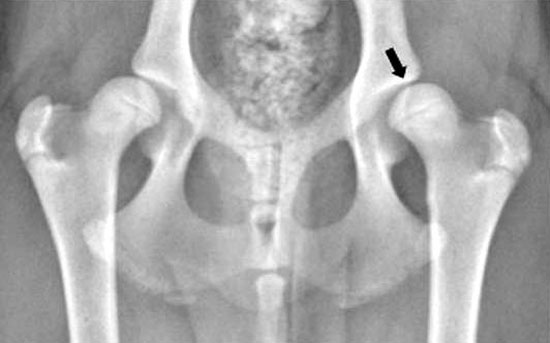

Displasia

dell'anca: La radiografia (raggi X) di un cane giovanile con

sublussazione di entrambe le articolazioni dell'anca secondaria a

displasia dell'anca. La testa del femore (freccia) è mal inserita

all'interno dell'acetabolo, indicando scarsa congruenza dell'anca. Non

vi è alcuna evidenza di malattia degenerativa delle articolazioni

(artrite).